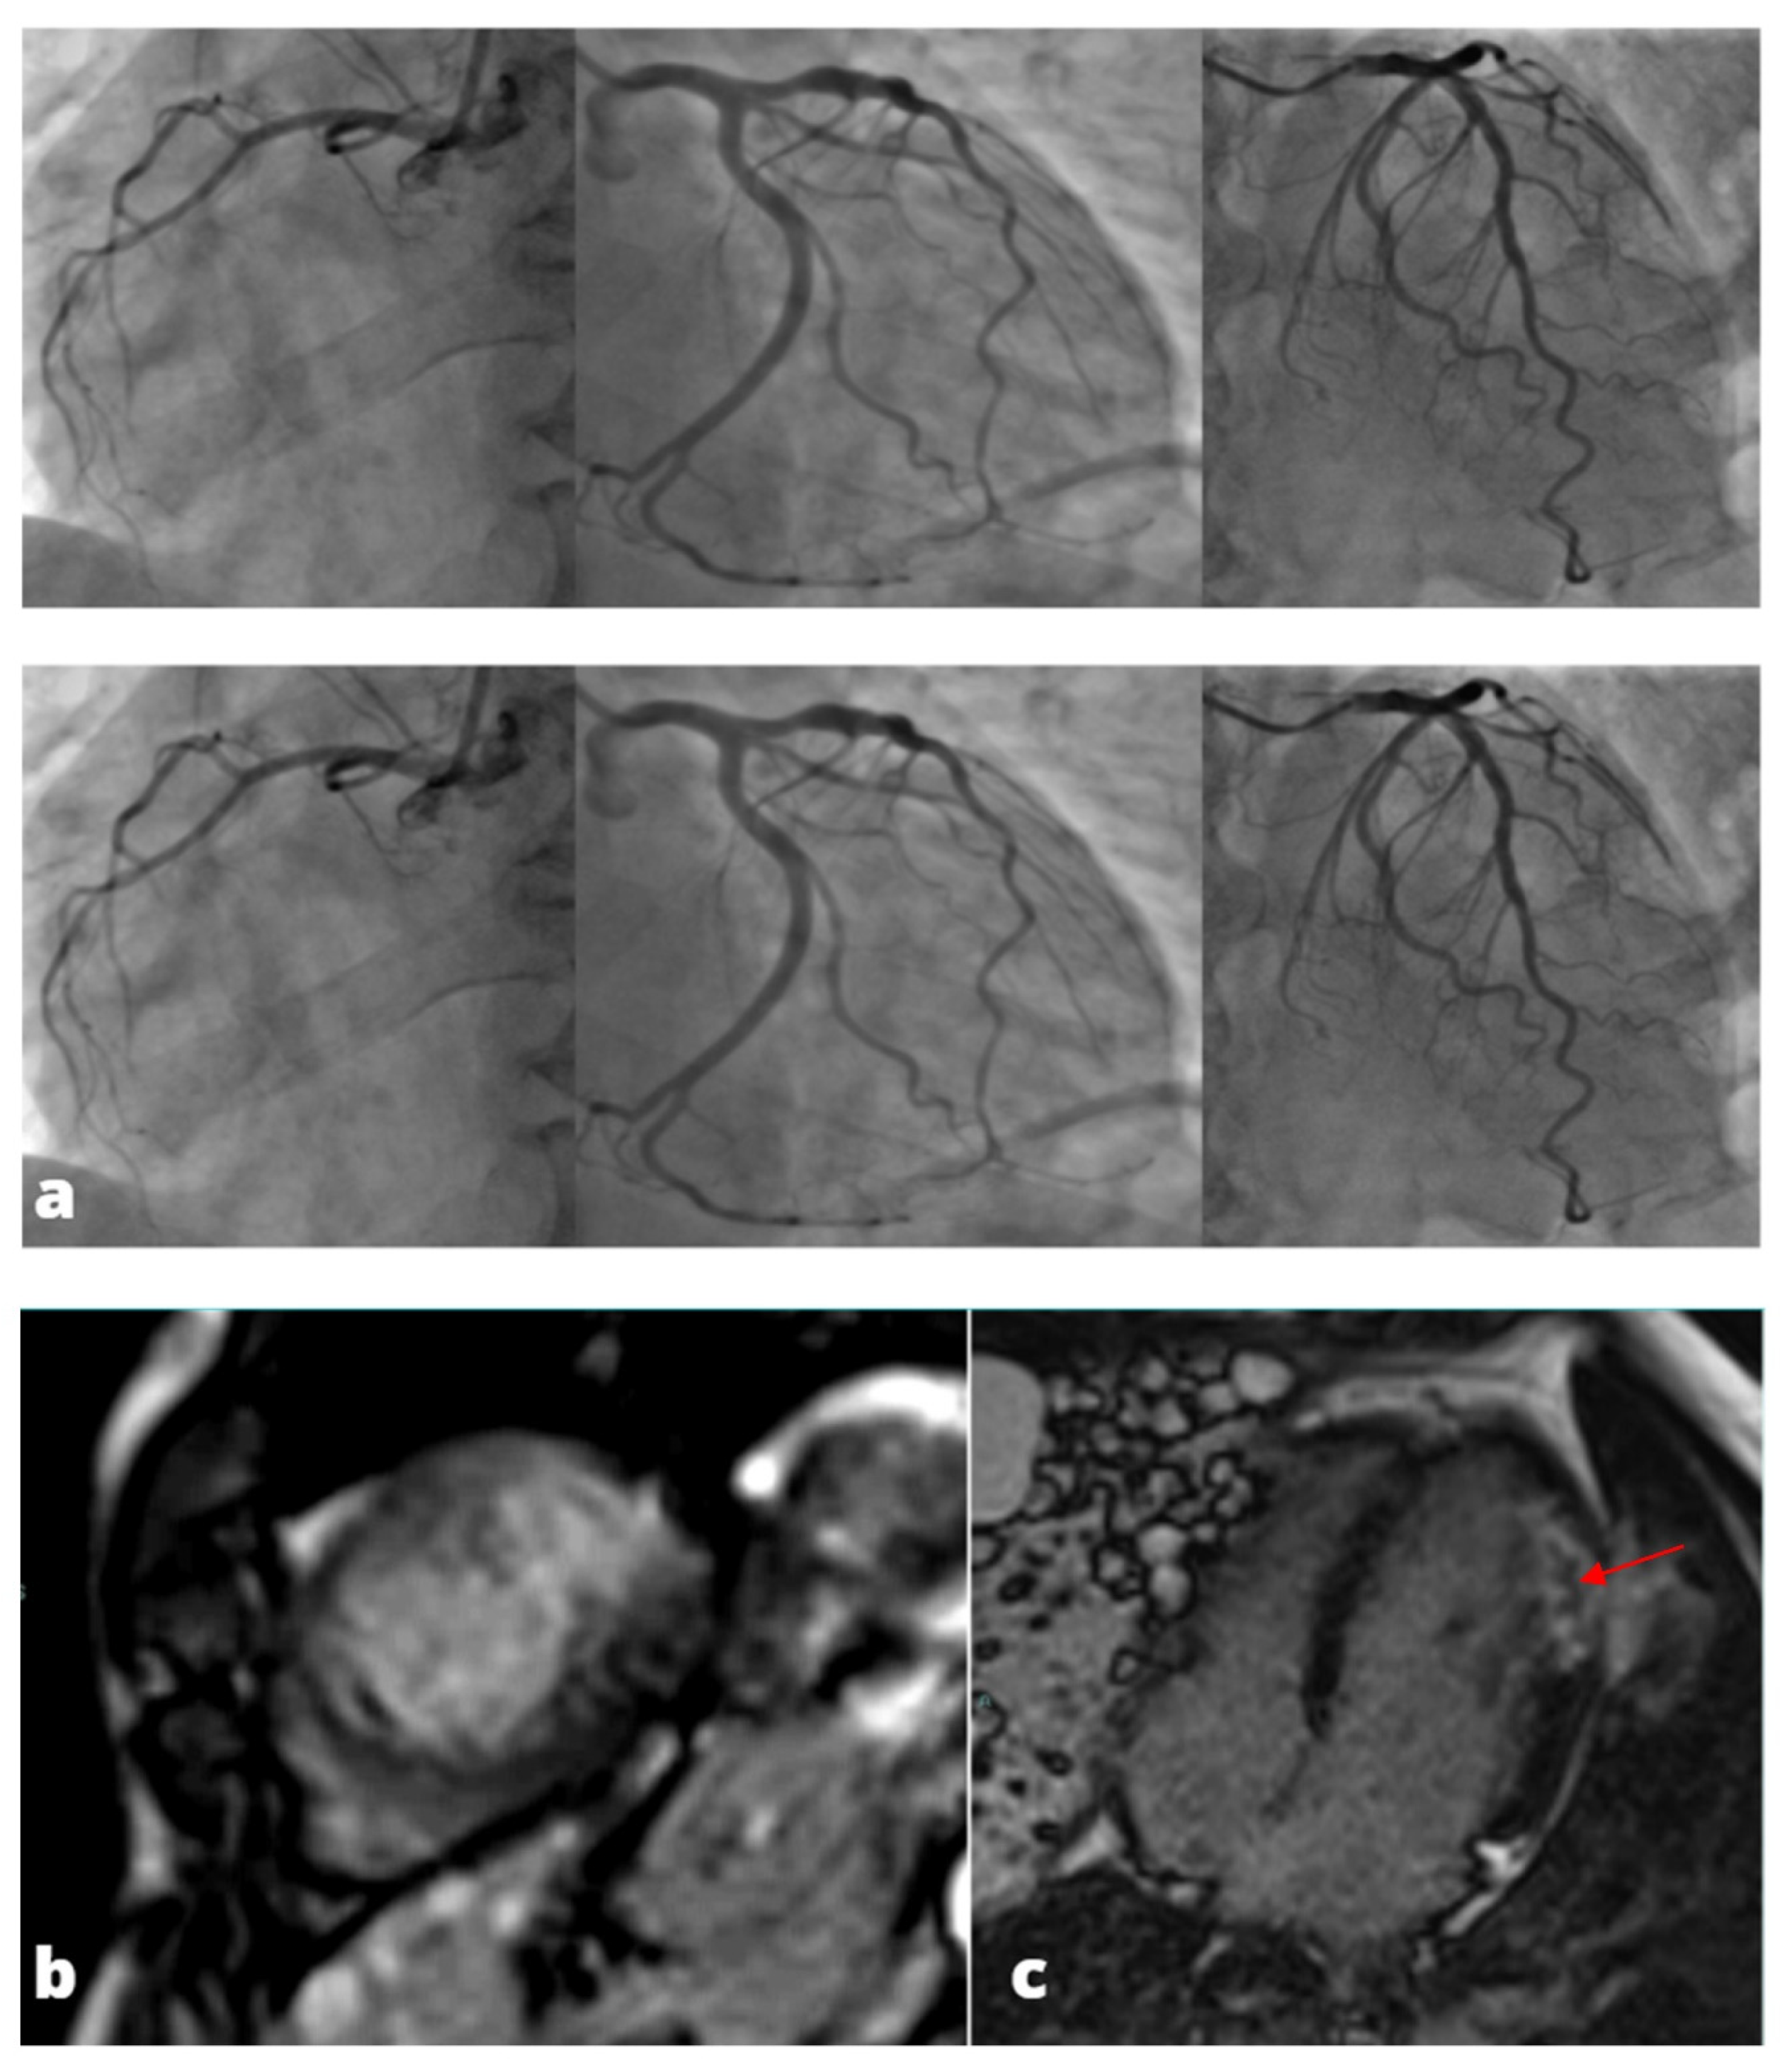

CT coronary angiography (CCTA) is not indicated in these patients [9,10] due to the presence of ECG alterations and enzyme elevation that were recorded, but it may be of value when diagnostic uncertainty remains after intravascular imaging. In this group of patients, CT can assess the presence of intramural hematoma, dissection and acute coronary plaque disease. A negative CT study is associated with excellent prognosis and it allows the remaining work-up of non-ischemic causes to be redirected. Moreover, a normal CT study also has important management implications because the use of antiplatelet and statin therapy can be considered pointless when the atherosclerotic wall changes are absent. However, it is important to note that CCTA may be less accurate in an acute setting because of general illness. Therefore, the prognostic implications of a negative CCTA may not apply to MINOCA patients (Figure 3).

Figure 3. MINOCA-Miocardial Infarct non obstructive coronaries. The patient presented to the emergency department with acute chest pain, ECG and cardiac enzymes suggestive of STEMI in the lateral wall of the left ventricle. The patient was readily referred to coronary angiography and cardiac catheterization showed absence of obstructive stenoses in the coronary tree (a). One day later a cardiac MRI was performed demonstrating a subacute ischemic scar in the lateral wall of the medium-apical left ventricle ((b)-LGE short axis view, (c)-LGE four chambers view). In the context of transmural late gadolinium enhancement, a constantly hypointense central area is present, representing a microvascular obstruction zone (red arrow). A cardiac CT was subsequently performed in order to assess coronary wall features and the presence of atherosclerosis. CT images in volume rendering (d) and multiplanar oblique reconstruction (e) demonstrated a non-calcified atherosclerotic alteration in an obtuse marginal vessel, serving the infarcted zone. A partly calcified atherosclerotic pathology was present in the anterior descending artery.